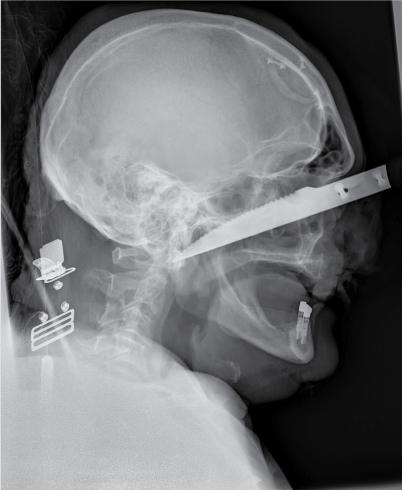

Because of the stable vital parameters we took the time to further investigate the knifeās trajectory. A plain X-ray showed the knife's position, outside the neurocranium, with the tip extending just anterior of the first cervical vertrebra (Figure 1 and Figure 2). To gain additional information regarding the structures in the face and the exact positioning of the knife a complementary enhanced CT scan with intravenous contrast was made (Figure 3). This scan showed the knife penetrating from the medial side of the orbita, along the maxillary sinus, through the medial pterygoid plate and nasopharynx, ending at the right anterior arch of C1. The eyeball and muscles are untouched, as well is the internal carotid artery.